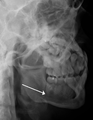

Nondisplaced fracture of the mandible

Plain film radiography

Traditionally, plain films of the mandible would be exposed but had lower sensitivity and specificity owing to overlap of structures. Views included AP (for parasymphsis), lateral oblique (body, ramus, angle, coronoid process) and Towne's (condyle) views. Condylar fractures can be especially difficult to identify, depending on the direction of condylar displacement or dislocation so multiple views of it are usually examined with two views at perpendicular angles.[10]